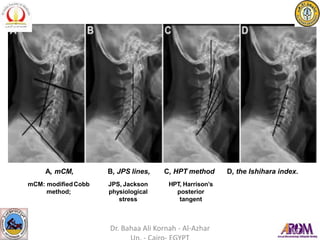

measuring CL include :

A. themodifiedCobb method

(mCM),

B. Jackson physiological stress

lines (JPS),

C. Harrison’s posterior tangent

method (HPT),

– theIshihara index.

A, mCM,

mCM: modifiedCobb

method;

B, JPS lines,

JPS, Jackson

physiological

stress

C, HPT method

HPT, Harrison’s

posterior

tangent

D, the Ishihara index.